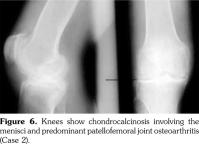

Case 2- A 39-year-old male patient presented with swelling of both knee joints. He also gave a history of recurrent painful swelling of knee joints and wrist joints for more than 10 years and was treated by an Ayurvedic physician. Other medical history or family history of medical problems were insignificant. There was a massive swelling of both knee joints with effusions, which was aspirated and the X-rays revealed calcification of the articular cartilages (Figure 5). A written informed consent was obtained from the patient.

He had chondrocalcinosis involving the menisci and hyaline cartilage, with predominant patellofemoral joint osteoarthritis. His blood investigations to find a metabolic cause for CC were negative.